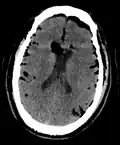

If there is a valve mechanism which allows air to enter the skull but prevents it from escaping, a tension pneumocephalus can occur (similar to what can happen in a tension pneumothorax).

CT scans of patients with a tension pneumocephalus typically show air that compresses the frontal lobes of the brain, which results in a tented appearance of the brain in the skull known as the Mount Fuji sign.[1][2][3] The name is derived from the resemblance of the brain to Mount Fuji in Japan, a volcano known for its symmetrical cone. In typical cases, there is a symmetrical depression near the midline (such as the crater of a volcano), due to intact bridging veins.[3] Its occurrence seems to be limited to tension pneumocephalus (not occurring in pneumocephalus without tension).[4] The sign was first described by a team of Japanese neurosurgeons.[5]